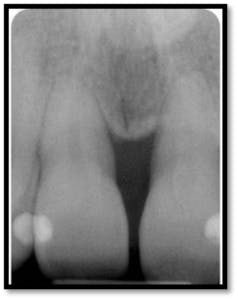

PD #26: 2mm M and F (above left), Great bone fill (above right)

Probing depths posterior and anterior teeth 3-4mm

Note the bone fill on the vertical defects of #8-9 and 18 and 19